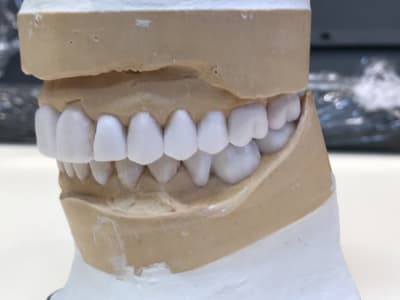

mon plan de ttt est le suivant extraction les dents aboluments non conservable (11-21-25) et tenter de garder le reste, puis réévaluer le cas apres surfacage et gingivectomie. Puis de couronner le reste: bridge 13 12 (11 21) 23, couronnes jumélées 14 15 16 17, bridge 24 (25) 26 27.

Question sur le wax up, faite vous un devis avant de faire un wax up ? le faite vous gratuitement pour expliquer son cas? car je me rend compte que c'est un sacré cout pour moi

D autant plus que ce n est pas un wax up ça , mais du coloriage blanc .

Pcq le probleme de ce cas est , entre autre , un decentrage lateral du au couple 17/ 47 .

Or il n a pas touché la 47 .

Donc ça ne sert à rien :-)

De + ,Les centrales du haut ,se sont decalées

Or il ne les a meme pas taillees , mais rempli les espaces .

Donc ça ne sert à rien .

A tout les coups il n y a pas eu de centree ( pour cela il aurait fallut limer la 47 ) .

Donc ça ne sert à rien

Le wax up n a d interet que pour proposer 1 nouvelle occlusion , pas pour embellir des faces vestibulaire ,en ayant ouvert la tige incisive .